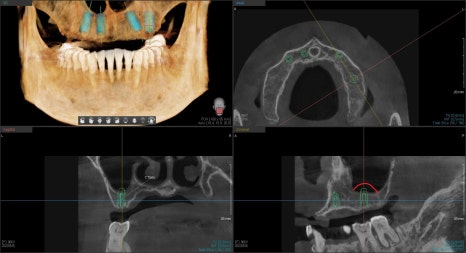

더 정확한 진단을 위해 3D CT를 촬영하여 시뮬레이션을 해보았습니다.

상악동의 모양, 접근 방법을 시뮬레이션 하며

빨간선까지 치조골 이식술을 계획하며

어느 부위에 임플란트 식립을 하는 것이 이상적인 것인지 와

환자분의 상황을 고려하며 여러 번 상담을 통해

치아의 개수, 보철물의 종류 등을 결정했습니다.

이 환자분 같은 경우는 중간에 보험 임플란트가 있기 때문에

PFM이라는 보철물로 진행하기로 했습니다.